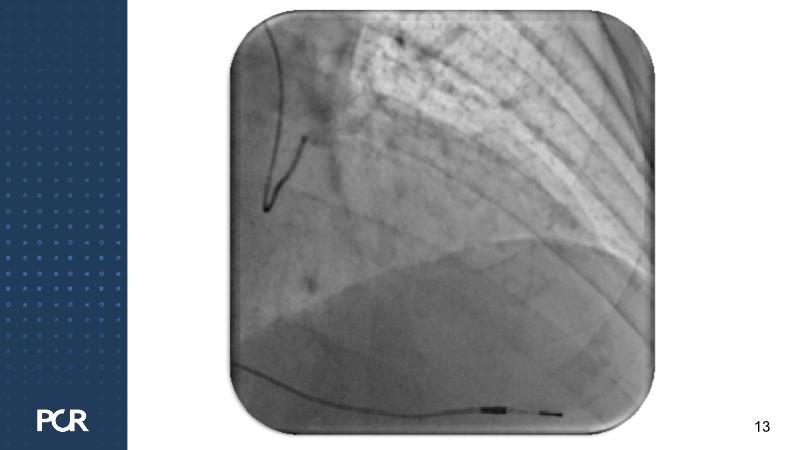

This session offers a comprehensive overview of the management of high bleeding risk (HBR) patients with multivessel disease. Through expert discussion and a live case demonstration featuring a complex elderly patient, it highlights how intracoronary imaging and physiology can guide procedural decisions and improve outcomes in this vulnerable population. The session also explores PCI strategies adapted to bleeding risk profiles, with a particular focus on the live case approach, including the use of sirolimus-eluting stents to optimise both procedural safety and long-term results.